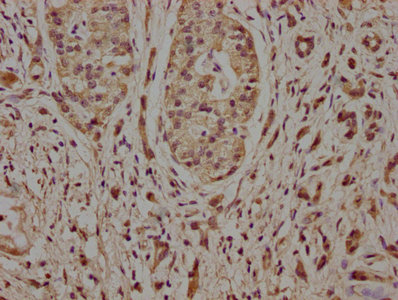

IHC image of CSB-PA822169LA01HU diluted at 1:100 and staining in paraffin-embedded human pancreatic cancer performed on a Leica BondTM system. After dewaxing and hydration, antigen retrieval was mediated by high pressure in a citrate buffer (pH 6.0). Section was blocked with 10% normal goat serum 30min at RT. Then primary antibody (1% BSA) was incubated at 4°C overnight. The primary is detected by a biotinylated secondary antibody and visualized using an HRP conjugated SP system.